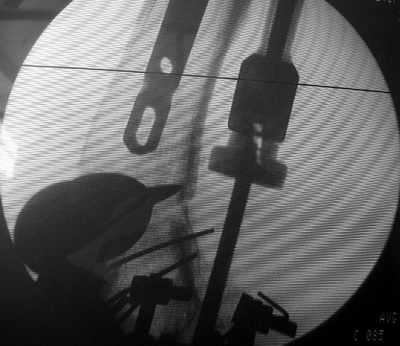

В итоге сделали антеградный остеосинтез. В дистракторе свежий перелом вправился сразу, а вот старый - оставил проблему, дистальный отлмомк остался все равно кзади. И гвоздь бы прошел кпереди от него, а ретроградный - перфорировал бы передний кортекс. Так что пришлось еще сделать чрескожную остеотомию через перелом, чтобы малость мобилизовать дистальный отломок. Снимки в прилжении.

The radiographs look excellent and a good outcome would be anticipated. The idea to osteotomize the femur shaft to compensate for the prior shaft malunion was clever and should work fine.

I can't actually see the osteotomy on either radiograph. Is it more proximal than we see in these radiographs or so well aligned as to be not visible?

The osteotomy was perfromed trough the fracture site. See the image.